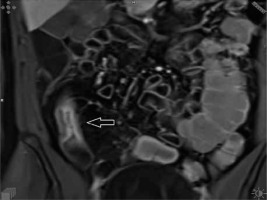

Figure 2

T1-weighted post-contrast coronal image showing stratification of the intestinal wall with trilaminar aspect of the bowel wall enhancement (arrowhead)